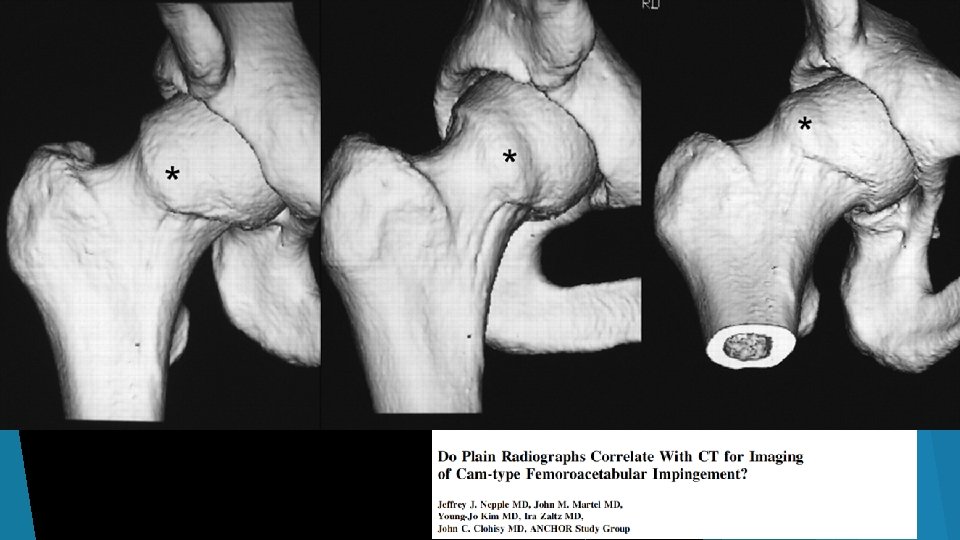

Radiographic Indicators of FAI

Center Edge Angle (Normal 25 -39, <15 = dysplasia) Alpha angle (Normal <50 deg) Crossover sign

Standard Views I recommend AP and Frog Leg views